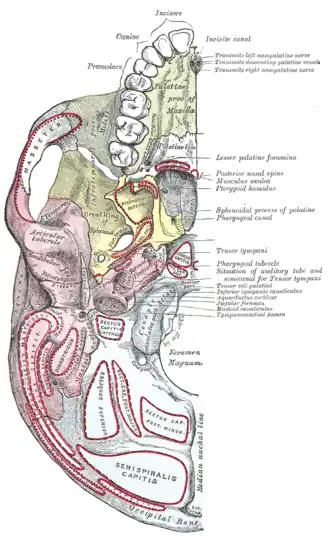

Inferior surface of maxilla. The bony palate and alveolar arch. (Palatine process labeled at bottom right.) | |

Inferior surface of maxilla. | |

Base of skull. Inferior surface.

Base of skull. Inferior surface. -